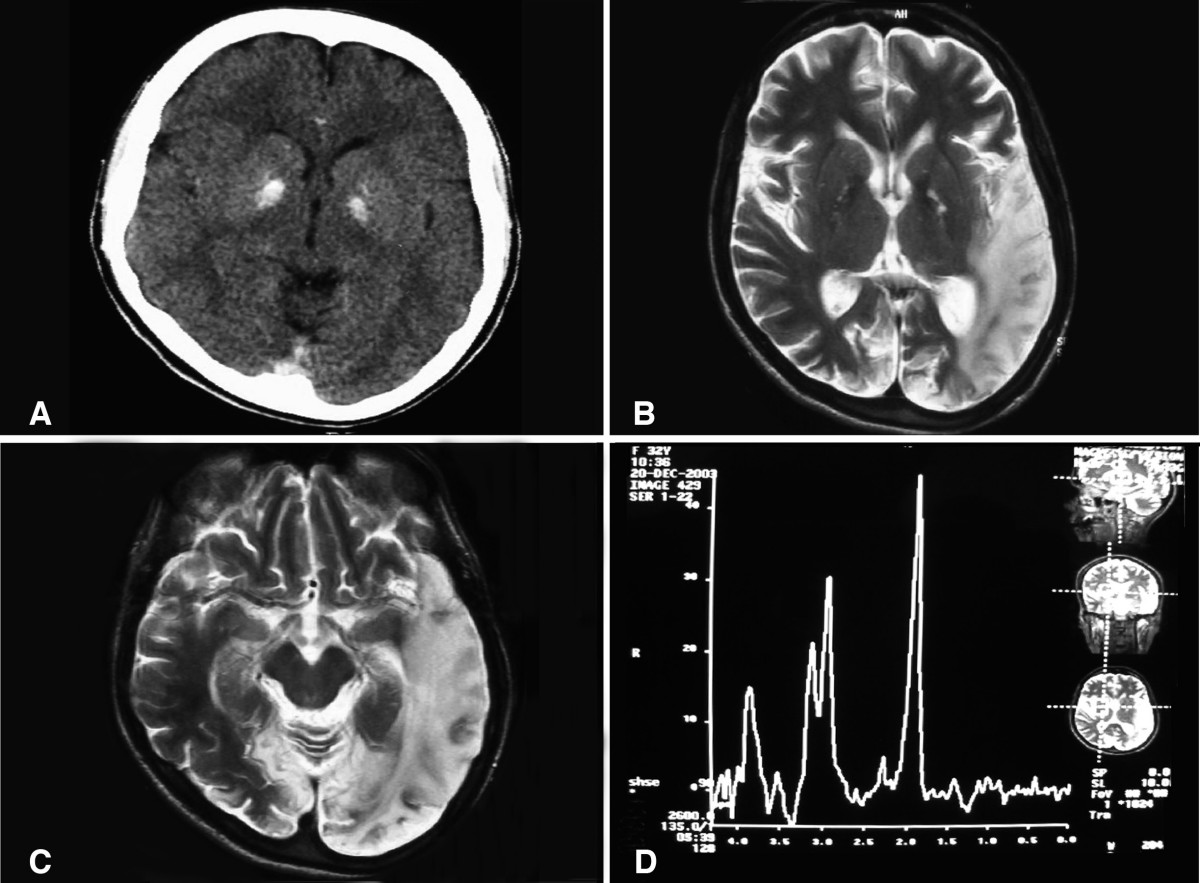

English: (a) A computed tomography brain scan showing bilateral basal ganglia calcification; the cerebellum shows prominent folia indicating mild cerebellar atrophy. (b) Axial T2 brain magnetic resonance image scan showing left temporo-parieto occipital ischemic lesion. (c) Axial T2 brain magnetic resonance image scan showing the extension of the parietal temporal region to the occipital lobe, and also showing a right occipital lesion. (d) Magnetic resonance spectroscopy showing inversion of J-coupling phenomenon at 1.3 ppm, indicating lactate peak. Abu-Amero et al. Journal of Medical Case Reports 2009 3:77 doi:10.1186/1752-1947-3-77 |

| Source | A patient with typical clinical features of mitochondrial encephalopathy, lactic acidosis and stroke-like episodes (MELAS) but without an obvious genetic cause: a case report |

| Author | Abu-Amero KK, Al-Dhalaan H, Bohlega S, Hellani A, Taylor RW. |